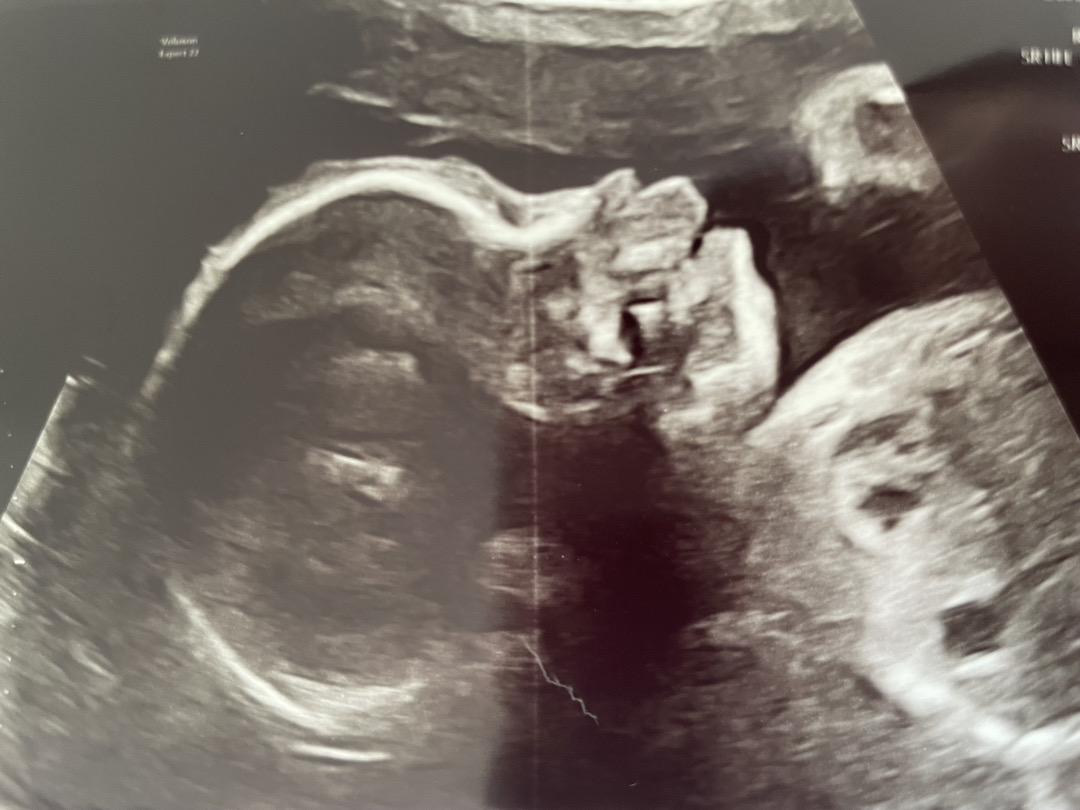

안녕하세요. 제가 해외거주중이라 두달에 한번? 정도 초음파를 찍어요. 여기는 입체초음파도 안찍어주구요. 초음파 찍는 위치 때문일까요 아기 윗입술이 갈수록 튀어나오고 코와 입술 경계도 애매하고, 턱도 자꾸 들어가네요. 남편이랑 저희집 모두 입모양, 턱 등등 이렇진 않은데, 예전초음파랑 비교하면 점점 이런 모습이 두드러져서요. 한국보자 자세한 진료들이 안되어서 답답한 마음에 올려봅니다.

저희 애 초음파도 보면 입이 쭉 나와있어요 ㅋㅋㅋ

각도마다 다르게보이는걸꺼에요 ㅎㅎ 이쁘게 만들어지고 있을테니 걱정마세요^^

각도따라 다른데 지금 뒤쪽에서 비춰진 각도라 그런것같아요 ㅋㅋㅋㅋ 그리고 아기들이 원래 아래턱이 다 작더라고요? 저 첫째 태어나고 아기 아래턱이 너무 작아서 무턱이면 어쩌지 정말 걱정했는데 쓸데없는 걱정이었어요^^